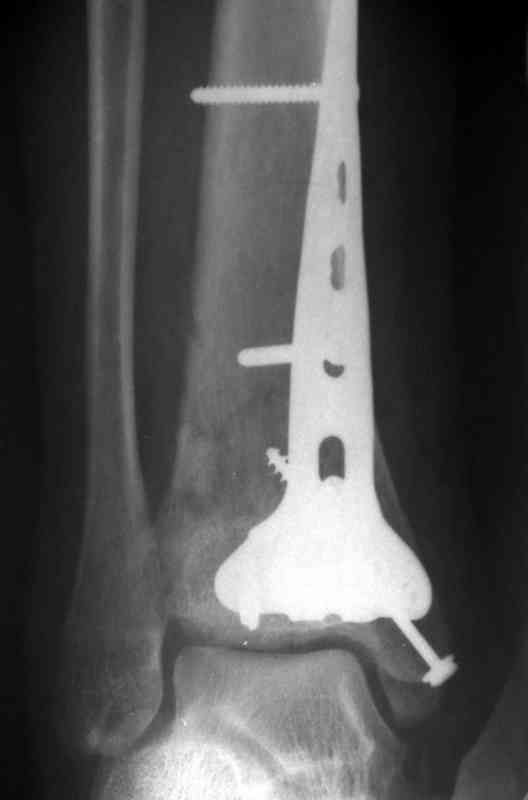

На рентгенограммах типичный перелом пилона по типу С-3. есть опыт до 100 открытых опреаций у нас в клинике. 20 примерно в год. Принцип один -все внутрисуставные переломы нуждаются в открытой репозиции и внутренней стабильной фиксации. При поступлении КТ не надо, так как получается только нагромождение костей. Истинной картины нет. Главное восстановить длину малоберцовой кости - это ключ к успеху. При поступлении меньше всего надо думать о сосудистых расстройствах, т.к. сама операция и репозиция даже сначала частичная даёт улучшение сосудитых нарушений. Причём очень быстро. Операция в 2этапа. При поступлении доступ позади наружной лодыжки, причём обязательно. После этого репозиция малоберцовой кости и фиксация пластиной 1/3 трубки под винт 3,5. Дренаж и любой аппарат наружной фиксации. Затем после спадения отёка на 5-7-10 день аппрат снимается и дугообразный разрез спереди от медиальной лодыжки 10-12 см. Главной чтобы расстояние между 1 и вторым разрезом было не меньше 7-8 см. Тогда не будет некрозов лоскутов. Таранная кость используется как матрица на неё укладываются отломки и фиксируются пицами. Ренг-контроль. Отломки лежат все отдельно, но ничего не высыпется. При переломах С-3 всегда нужна костная пластика (из крыла). Фиксация пластиной лист клевера простой или LCP. Гипс не нужен. Дренаж до 48 часов. Операция длится 3-4 часа обязательно без жгута. Посылаю примерно такой же случай.

Послала ещё два снимка, если не пройдут, пошлю ещё. Дрягин. Если есть вопросы, готов ответить.

Посылаю результат лечения предыдущего больного через год.

С уважением Дрягин